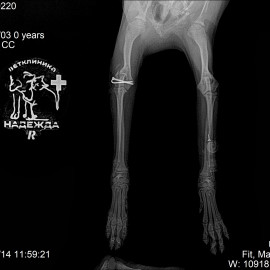

Пациент - собака по кличке Барик.

Обратились в клинику с жалобами на отсутствие опороспособности на правую переднюю лапу.

Были проведены осмотр и рентгенологическое исследование. Поставлен диагноз: перелом правого плеча. Проведена операция: остеосинтез правой плечевой кости.

Снимки 2-3 после операции.